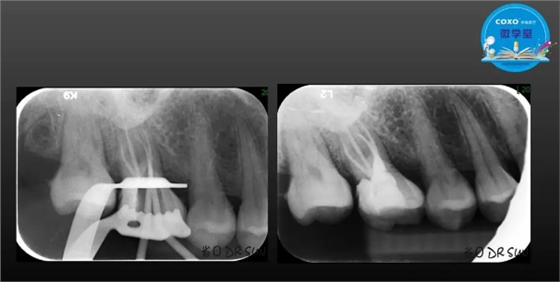

主任医师,牙体牙髓副主任, 广东省口腔医院牙体牙髓科 主任医师。2003年硕士研究生毕业,研究方向为牙体牙髓病学,擅长于牙体牙髓病的诊断、龋齿、牙髓炎、根尖周病的治疗以及前牙美容修复。